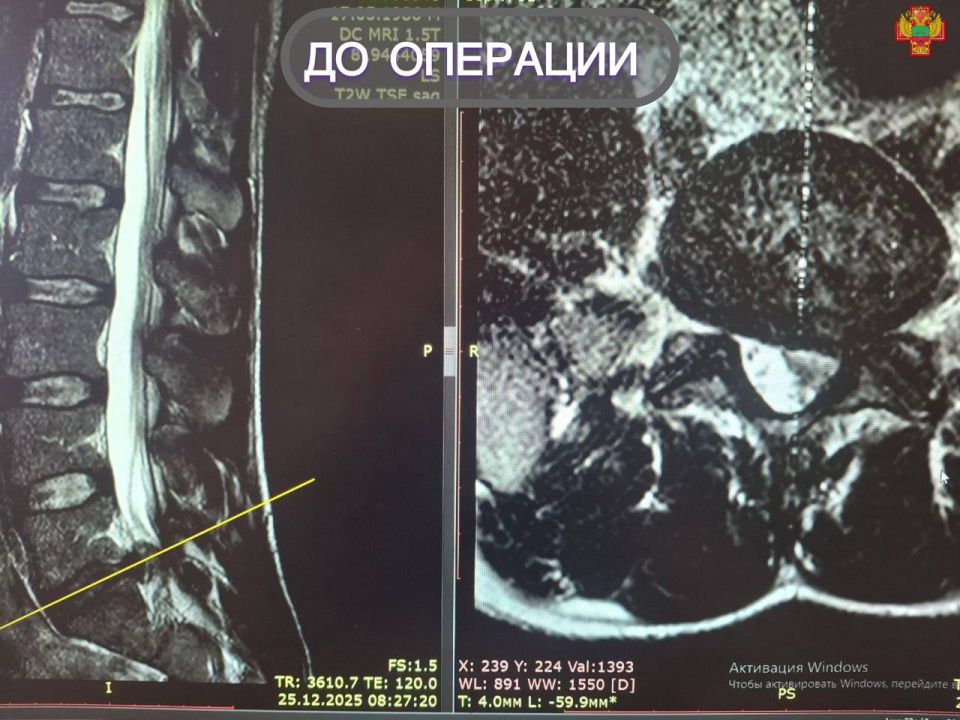

Выявленная на снимке МРТ секвестрированная грыжа поясничного отдела позвоночника требовала срочного вмешательства, поскольку создавала угрозу серьезных осложнений.

Нейрохирурги успешно провели микрохирургическое удаление грыжи. Оперирующий нейрохирург Михаил Еремеев отметил, микродискэктомия является «золотым стандартом» лечения грыж позвоночника.

«Благодаря современному оборудованию и небольшому разрезу мы устранили компрессию позвоночного канала.Такой минимально инвазивный метод позволяет быстро и эффективно устранить причину боли, сократить срок пребывания в стационаре, снизить риск инфекций и тем самым ускорить восстановление. Мы рады видеть, как пациенты возвращаются к активной жизни без страданий»,